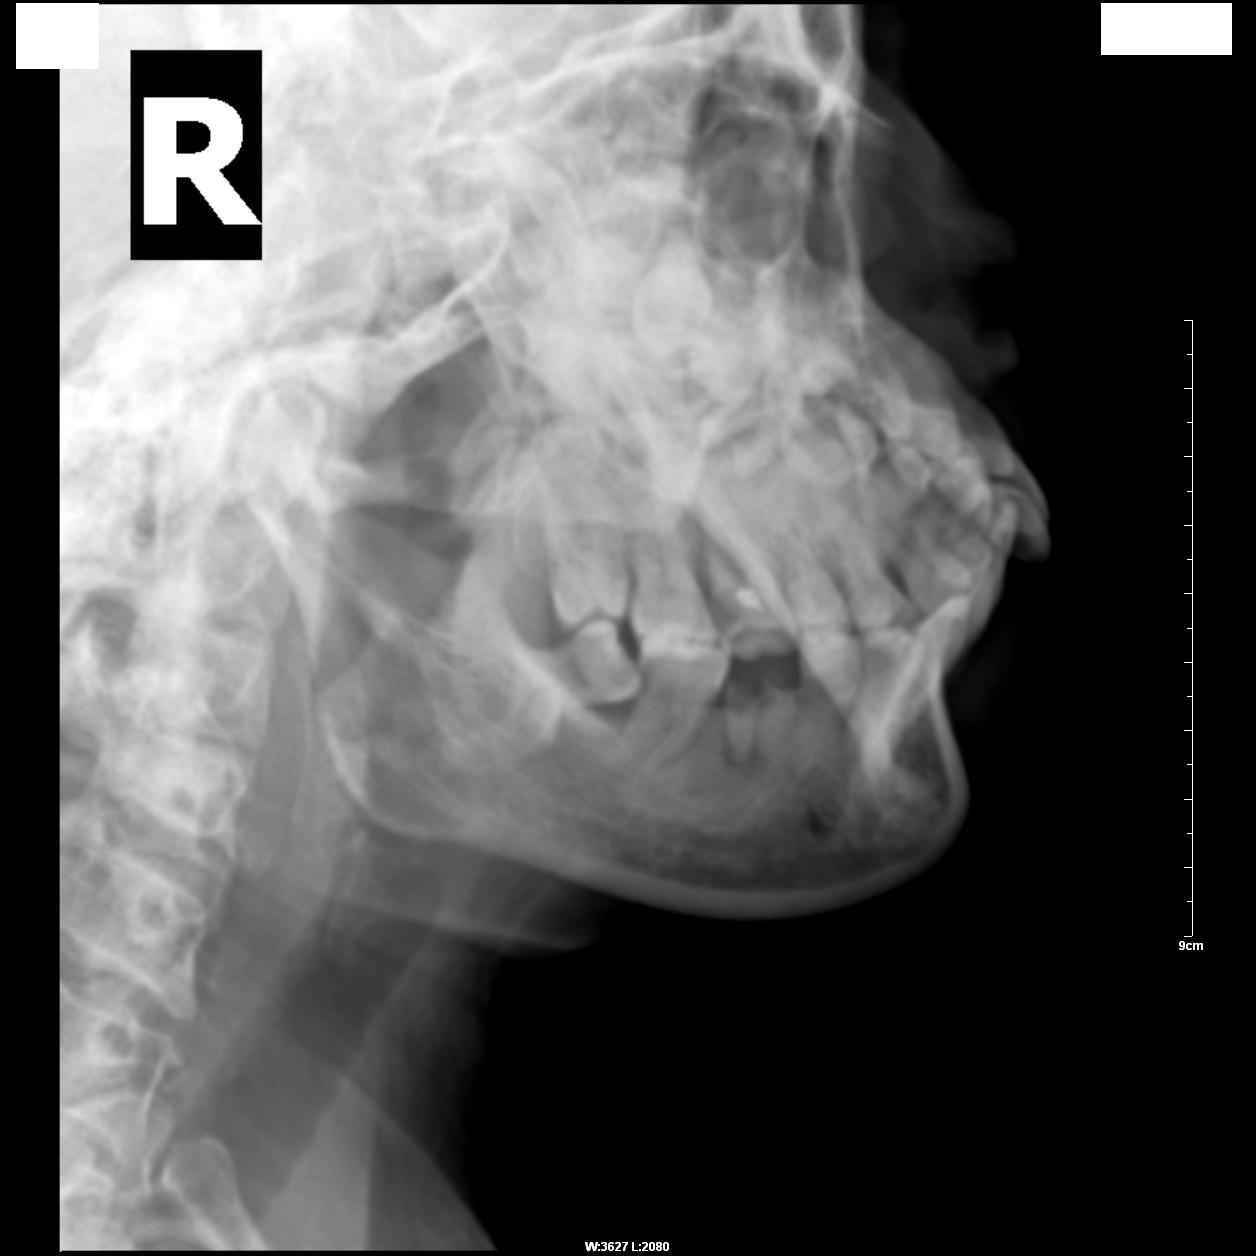

标题: X3841:阻生齿、龋齿、根尖周围炎。 [打印本页]

标题: X3841:阻生齿、龋齿、根尖周围炎。

患者,女,39岁,右侧下牙齿疼痛不适。

x线表现:右侧第3下磨牙向前倾斜,其部分牙冠与第2下磨牙颈相抵触;第1下磨牙冠显示缺损,其根尖处显示局限性密度减低影。